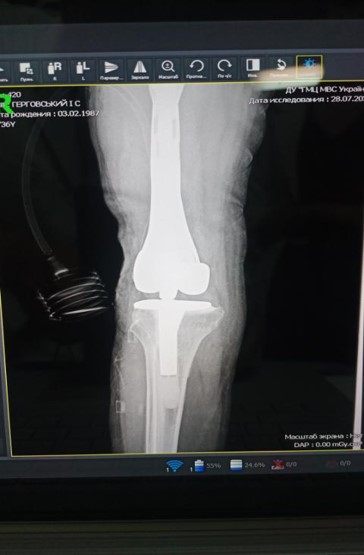

Приклад 2. Хвора  М. 68 років. Діагноз: лівобічний деформівний IVст. гонартроз, стан після ТЕП лівого КС (2014р.). Під час виконання оперативного втручання компоненти ендопротезу встановлені в варусному положенні. Асептична нестабільність компонентів ендопротеза, тотальна  нестабільність зв’язкового апарату компонентів колінного суглоба (2017 р.)  Хворій виконано ревізійне ендопротезування: видалення компонентів ендопротезу, виявлений дефект виростку великогомілкової кістки тип Т2А за класифікацією АОRI [G.A. Engh, C.H. Rorabeck, 1997]. Враховуючи стан зв’язкового апарату використаний зв’язаний ендопротез типу Hinch.